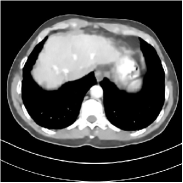

Fig. 3 illustrates the image evolution over SUPER layers (i.e., with evolving network weights in the iterative reconstruction process) for one test case, when using SUPER-WRN-ULTRA. It is apparent that in the early SUPER layers, the proposed SUPER-WRN-ULTRA method mainly removes noise and artifacts, while later SUPER layers mainly reconstruct details such as the bone structures shown in the zoom-in box. A similar behaviour is observed with FBPConvNet-based SUPER methods, which are shown in the supplement (Figs. 13 and 14).

Refer to caption Refer to caption Layer 1RMSE =27.44 HURefer to caption Refer to caption Layer 5RMSE = 26.03 HU

Refer to caption Refer to caption Layer 11RMSE = 25.91HURefer to caption Refer to caption Reference

Figure 3: Image evolution over SUPER layers using the SUPER-WRN-ULTRA method. RMSE values are also indicated.